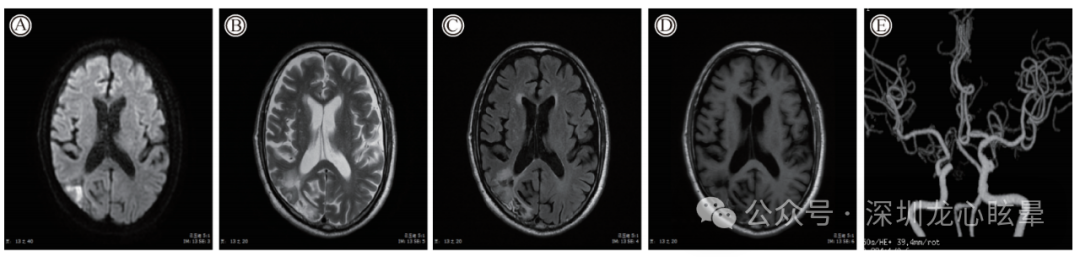

小脑病变引起的中枢血管源性孤立性眩晕:最常受累的血管是小脑后下动脉(posterior inferior cerebellar artery , PICA)和小脑前下动脉(anterior inferior cerebellar artery , AICA),而小脑上动脉(superior cerebellar artery , SCA)供血区病变颇为少见。由 PICA 供血的小脑小结叶、扁桃体、小脑下脚;由AICA 供血的前庭神经核、前庭神经入颅处、绒球以及由基底动脉供应的舌下神经前置核(NPH)等部位的孤立性梗死均可导致孤立性眩晕。

图2 一例右侧小脑急性脑梗死

(1)PICA供血区: 小脑小结、小舌及扁桃体受累均可表现孤立性眩晕和姿势平衡障碍,其中以小结病变引起的孤立性中枢性前庭综合征最为常见。小结损害可造成同侧前庭神经核失抑制、速度储存机制调控及空间定位功能异常,可以发现快相朝向病灶侧的水平自发眼震、倒错性摇头眼震、病理性眼偏斜反应及主观垂直视觉偏斜等体征;小舌与扁桃体病变可以发现单向凝视诱发眼震与倒错性摇头眼震,小舌病变还可见异常的视动性眼震,而朝向病灶侧平稳跟踪受损可见于单侧扁桃体病变。头脉冲试验是识别表现为“假性前庭神经炎”的PICA内侧支梗死最有效的床旁检查手段,其检查结果通常为阴性。

(1)孤立性小脑小结梗死:小脑小结由 PICA 供血,位于小脑的中线部位,它与同侧前庭神经核有着密切联系,同时接受来自迷路的传入信号,控制眼动并调节姿势平衡。孤立的小结梗死非常少见,查体可见单向自发眼震以及向健侧倾倒。自发眼震的方向朝向患侧,还可出现周期交替性眼震、倒错摇头眼震和阵发性中枢性位置性眼震等表现。这与小结对重力惯性的前庭信号处理、前庭二级神经元的抑制功能和速度储存机制受损有关。大部分小结梗死临床表现与急性前庭外周病变类似,但其 HIT和双温试验正常、严重的姿势不稳是与前庭外周病变的重要鉴别点。

(2)孤立性小脑扁桃体梗死:孤立的小脑扁桃体(PICA 供血)梗死罕见,其表现为以下体征:①方向向患侧的自发眼震;并出现反跳性眼震;②GEN,向患侧注视时强度更大;③平稳跟踪损害;④双温、HIT、前庭眼反射、扫视正常。部分患者还出现主观垂直视觉向健侧偏斜,提示扁桃体不仅与半规管通路的张力不平衡(导致自发眼震)有关,而且对耳石系统也有一定的控制作用。

(3)孤立性小脑下脚(ICP)梗死:ICP包含了出入小脑的各种纤维,主要整合本体感觉和前庭的信息。前庭小脑到前庭神经核的传入和传出纤维都经过ICP,所以孤立性ICP损伤表现为眩晕和姿势不稳。主要表现为向患侧的自发眼震,患侧平稳跟踪异常,健侧 OTR 和主观垂直视觉偏斜。

(4)孤立性小脑绒球梗死:小脑绒球参与控制凝视稳定、平稳跟踪和前庭刺激诱发的眼动。单纯绒球梗死少见,症状为突发眩晕和姿势不稳;查体自发眼震朝向患侧,无眼扭转、头偏斜及主观垂直视觉偏斜。HIT 显示健侧轻度纠正性扫视,双温试验无异常。在转椅检查中,低频水平刺激时前庭眼反射增益增高,高频刺激时出现双侧前庭眼反射不对称的增益减低。